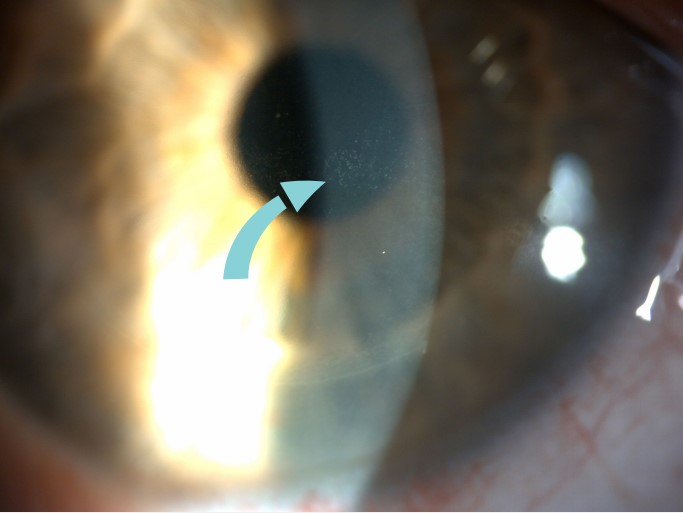

- Slit Lamp Exam